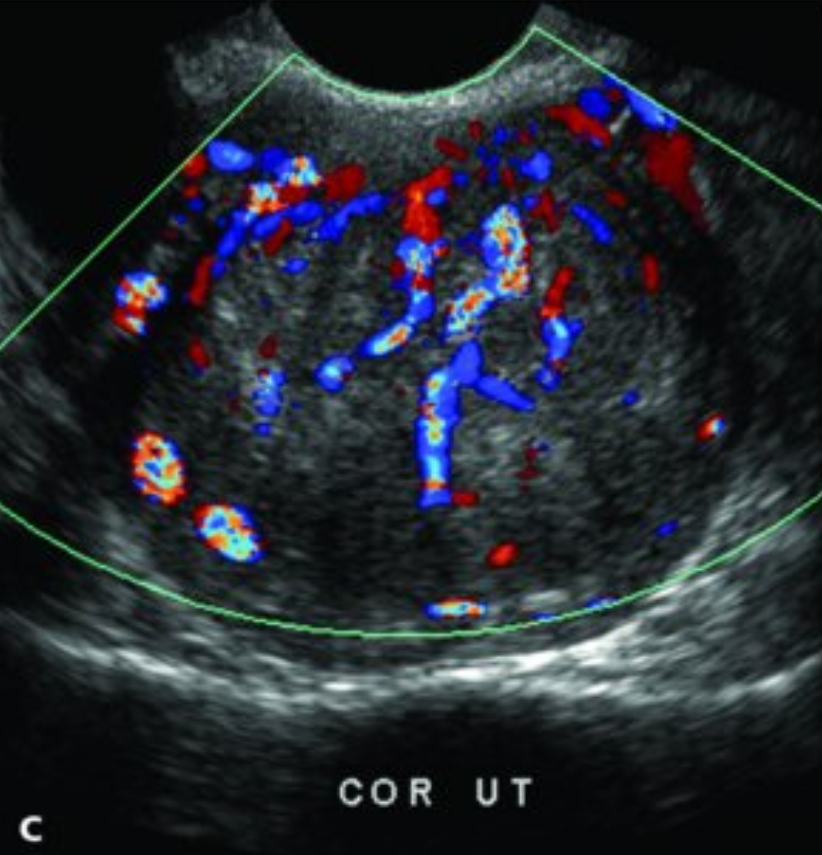

Ultrasound

• US in 2 weeks to assess the uterine size